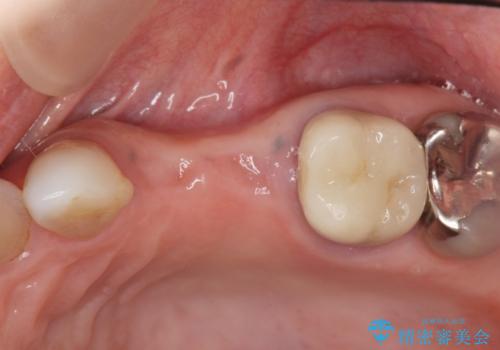

- 97.9万円(インプラント×2・アバットメント×2・仮歯×2・ジルコニアクラウン×2・骨造成)費用は治療当時の料金となります

今回はが原因で失われてしまった骨の幅を回復することで長期的な予後を見込めるインプラント治療を行うことができました。